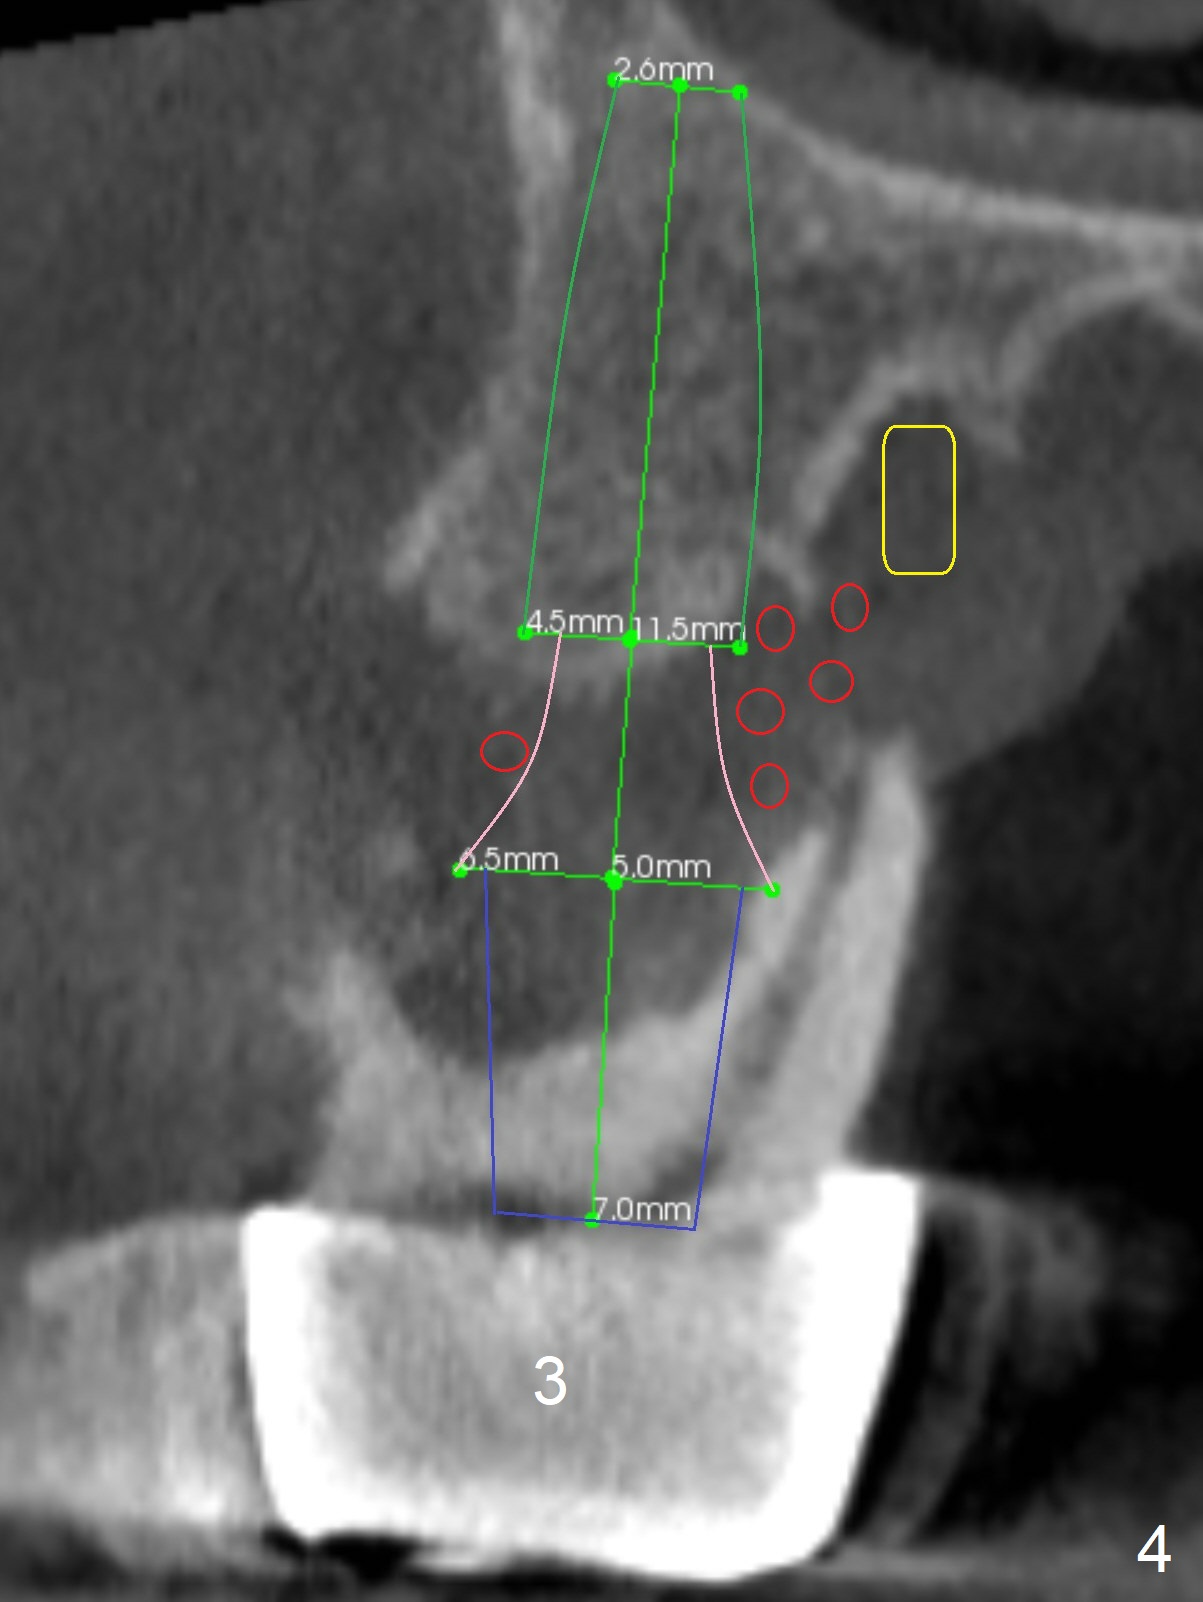

Extract #2 or remove #3-5 FPD first whichever is looser. Use the other as reference guide. Place Osteogen plug in the palatal socket of #2 ad 3 (Fig.3,4 yellow box) and allograft around the implants (red circles).